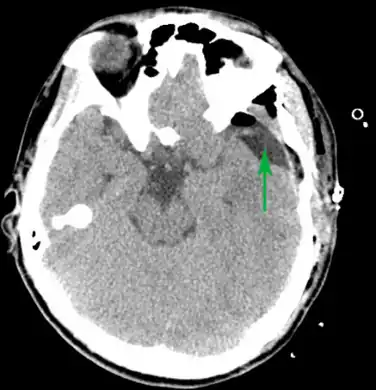

Male with complicated arachnoid cyst

Arachnoid cyst as seen on a CT image of the brain

Axial CT showing a typical arachnoid cyst left temporal

Diagnosis is principally by MRI. Frequently, arachnoid cysts are incidental findings on MRI scans performed for other clinical reasons. In practice, diagnosis of symptomatic arachnoid cysts requires symptoms to be present, and many with the disorder never develop symptoms.